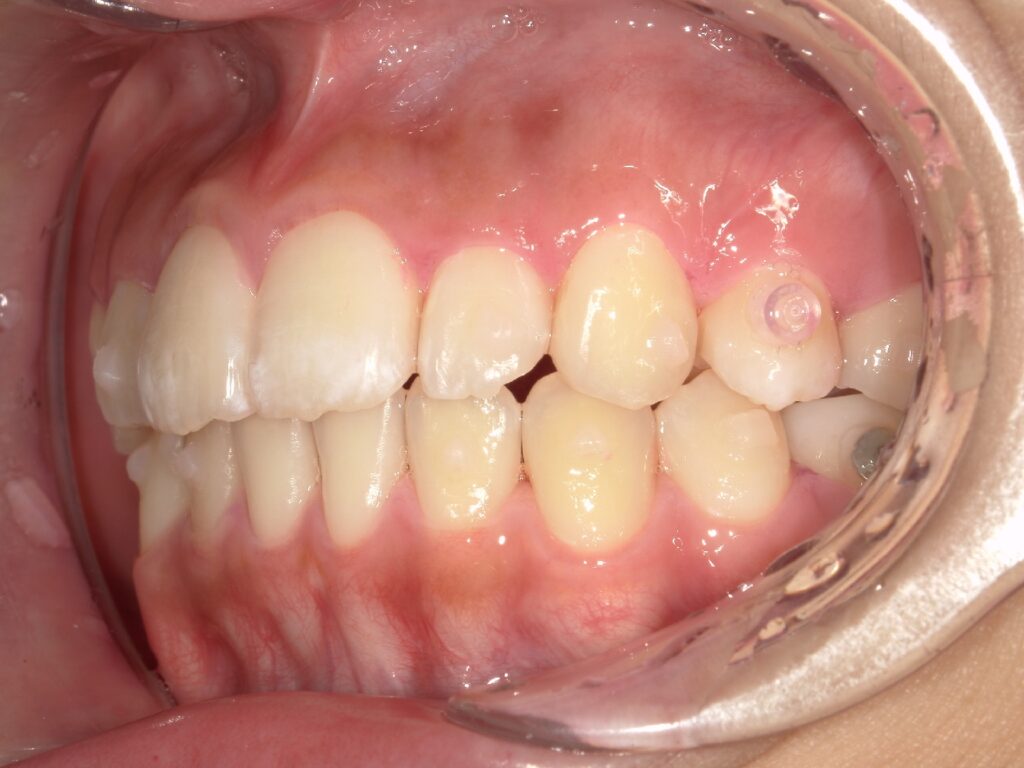

上顎の前歯が大きく突出しています

明らかに前歯の突出感が改善し、患者様はこの時点でとても喜ばれていました

矯正治療終了時 部分矯正ということもあり、短期間で矯正治療を終了することができました